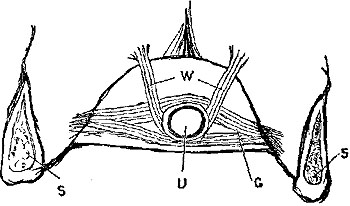

Ligature above Omohyoid.—Using the anterior border of the sterno-mastoid as a guide, but leaving it gradually above to a little nearer the mesial line, an incision (Plate IV. fig. 1), varying in length according to the depth of fat and cellular tissue in the neck, but with its central point opposite the upper border of the cricoid cartilage, must be made through skin, platysma, and superficial fascia. While making the incision the head should be held back, and the face slightly turned to the opposite side; the parts being now relaxed by position, the edges of the wound must be held apart by blunt hooks or copper spatulæ, and the deep fascia carefully divided over the vessel, which will be recognised by the pulsation. It may be noted here that even in thin subjects the sterno-mastoid edge invariably overlaps the vessel, though in many anatomical diagrams it would appear to be in part subcutaneous.

The descendens noni may possibly be seen, but this is by no means invariably the case, crossing the sheath of the vessel very gradually from without inwards in its progress down the neck. It must be carefully displaced outwards.

The sheath of the vessel is then to be cautiously opened to the extent of about half an inch. The internal jugular vein, possibly much distended, may overlap the artery on its outer side, and will require to be pressed, emptied, and held out of the way. A small portion of the artery being thoroughly separated from the sheath, the aneurism-needle must be passed from without inwards to avoid the vein, and keep as close to the artery as possible to avoid the vagus.

The tendon of the omohyoid muscle, or, in muscular subjects, a portion of its anterior fleshy belly, may be{30} seen crossing the vessel from above downwards and outwards at the lower angle of the wound.

An enlarged lymphatic gland has occasionally given much trouble, by being mistaken for the vessel and cleaned, while the ligature has even been placed on a carefully isolated fasciculus of muscular fibres.

Ligature of Carotid below the Omohyoid.—An incision in precisely the same direction as the former, but at a slightly lower level, is required, but the dissection is rather more difficult. The edge of the sterno-mastoid when exposed must be drawn outwards; the sterno-hyoid and thyroid inwards; the omohyoid upwards; the sheath opened, and the descendens noni or its branches drawn to the tracheal side. The jugular vein and vagus are both at the outer side, and must be avoided, while the inferior thyroid artery and sympathetic nerve both lie behind the vessel, and may be included in the ligature if care be not taken.

1. Ligature of External Carotid.—Head in same position as for the common carotid. A straight incision parallel with the anterior edge of sterno-mastoid, but about half an inch in front of it, must begin almost at angle of jaw, and extend downwards nearly to the level of the thyroid cartilage. Cautiously divide skin, platysma, and fascia; the lower end of the parotid must be pulled upwards, and the veins, which are numerous, cautiously separated. The anterior border of the sterno-mastoid must be pulled backwards, and the digastric and stylo-hyoid forwards and inwards. The superior laryngeal nerve which lies behind the vessel must be avoided.

2. Ligature of Lingual.—To secure this vessel either before it becomes concealed by the hyo-glossus, or after it is under the muscle, a curved incision is necessary, following the line of the hyoid bone, and especially of its greater cornu, but a line or two above its upper border. After the skin and platysma are divided, the posterior belly of the digastric must be{33} recognised, which again will guide to the posterior edge of the hyo-glossus. The edge of the sub-maxillary gland may very probably require to be raised out of the way. The artery can then be secured, either before it dips under the hyo-glossus muscle, or after it has done so, by the division of a few of its fibres on a director. Care is needed to avoid injury of the hypo-glossal nerve, which lies above the muscle.